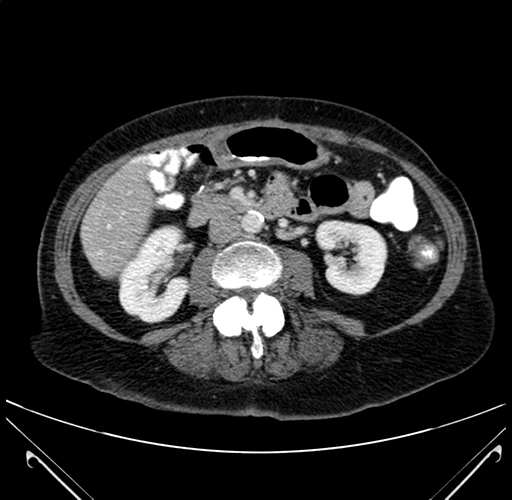

Axial Venous